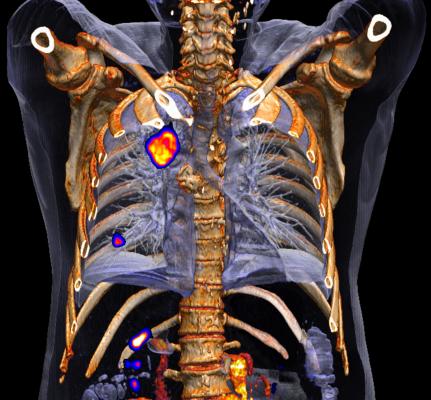

June 12, 2015 - Siemens' PETNET Solutions Inc. has entered into a nationwide agreement with U.K.-based Blue Earth Diagnostics Ltd. for the exclusive commercial manufacturing and distribution of Fluciclovine (18F), an investigational positron emission tomography and computed tomography (PET/CT) radiopharmaceutical. Fluciclovine (18F) is being studied for prostate imaging in clinical trials conducted in the United States, Japan, Italy, Norway, Sweden and Finland. The F-18-based radiopharmaceutical has a long half-life, which may facilitate its geographical distribution to clinical trial sites and then to clinical imaging centers once it gains approval from the U.S. Food and Drug Administration (FDA).

Prostate cancer is the second-leading cause of cancer in men worldwide, with 220,800 men expected to be diagnosed in 2015 in the U.S. alone. Currently, approved diagnostic options for prostate cancer include PET/CT scans using an injectable radiopharmaceutical to evaluate the extent of metastatic disease specifically for soft tissues and/or bony anatomy.